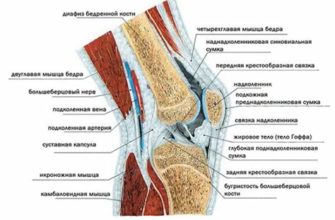

Причины и лечение травм коленного сустава